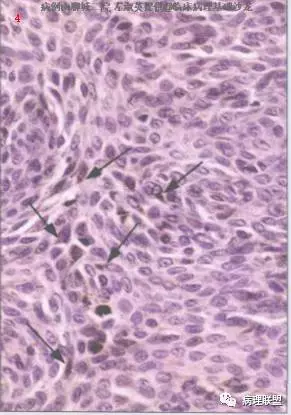

@左淑英 左老师,病例1,应该是汗腺来源,,考虑为汗孔瘤,细胞形成突起突入真皮,与表皮相连,第二张图箭头指向表示导管分化的结构,第三张图显示其纤维血管性间质,第四张图显示其有色素沉着,不知道对不对,今天我也遇着一个皮肤病例,您也给看看@左淑英

汗孔瘤、汗腺棘皮瘤、汗腺螺旋管腺瘤,三者细胞起源类似,细胞鳞不鳞、腺不腺,还象肌上皮。所以细胞成分可单一,也可复合存在。

淫荡点看,表皮如嘴唇,舌头抿在嘴里,顶多鼓一点,是汗孔瘤。舌头伸出嘴外,还带点似断不断、似滴不滴的哈喇汁,是汗腺棘皮瘤。哈喇汁滴到真皮里,一坨一坨地,就是螺旋管瘤。

@赖娇 不一样的,一个局限在表皮内看那张切片图就可以看到,细胞都是一样的,如我师父说的 ,比喻的简单明了,细胞都是那种空空的样子,汗腺棘皮瘤是汗孔瘤的一个亚型,有人这样认为,

@左淑英 左老师,汗1考虑单纯汗腺棘皮瘤;汗2考虑色素性汗孔瘤。